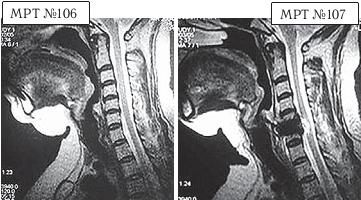

На МРТ №°103 наблюдается грыжа межпозвонкового диска в сегменте LIV-LV, частично компенсированная спондилёзом, гипертрофия задней продольной связки и выраженный эпидурит на данном уровне. В сегменте LV-SI наблюдается протрузия межпозвонкового диска, компенсированная спондилёзом. На уровне этих же сегментов наблюдается рубцовоспаечный процесс, как следствие перенесённой хирургической операции — ламинэктомии, проведённой в сегментах (LIV-LV, LV-SI), с целью устранения грыжи межпозвонковых дисков и декомпрессии спинномозговых корешков на данных уровнях. Приведённый ниже случай является показательным примером, как пациентка попала к недобросовестному хирургу, который сделал ей абсолютно необоснованную операцию. ![]() На МРТ № 104 наблюдается начальная стадия дегенеративного процесса в шейном отделе позвоночника, протрузия межпозвонкового диска в сегменте CVI—CVII. На МРТ № 105 наблюдается состояние после проведённой тотальной дискэктомии с передним межтеловым спондилодезом в сегменте CV—CVII, выпрямление физиологического лордоза, абсолютный стеноз спинномозгового канала с блоком ликворных путей, секвестрированные грыжи (с краниальной миграцией секвестров) в сегментах CIV-CV, CV-CVI, CVII-ThI. Состояние пациентки после операции ухудшилось, а в течение последующего года — значительно усугубилось. В данном конкретном случае не совсем понятно, зачем сделали эту операцию? Дооперационные жалобы больной были больше сосудистого характера. Прямых показаний к операции просто не было! Если бы данная пациентка прошла медикаментозное лечение у невропатолога, без хирургического вмешательства, то сейчас её здоровье было бы намного лучше, да и будущее бы не вызывало опасений в плане последующих осложнений. Вот ещё трагический случай во время проведения необоснованной операции. ![]() На МРТ № 106 состояние шейного отдела пациентки до операции. Наблюдается сглаженность физиологического лордоза, ликворные пути свободны, компенсированные протрузии межпозвонковых дисков в сегментах СIII—СIV На МРТ № 107 состояние шейного отдела той же пациентки после дискэктомии с межтеловым спондилодезом в сегменте CV—CVI, кроме того наблюдается травма спинного мозга на данном уровне хирургической фрезой. Если до операции у данной пациентки были незначительные вертебробазилярные нарушения, то после… Травма спинного мозга хирургической фрезой — это, конечно, трагическая случайность. Ведь от ошибок никто не застрахован и добросовестный врач никогда не даст гарантии на положительный исход любого вида лечения. Но в данном случае проведение самой операции было абсолютно необоснованным, фактически она превратила нормального человека в инвалида. Следующий пример также демонстрирует, какие бывают последствия после дискэктомии с межтеловым спондилодезом. |